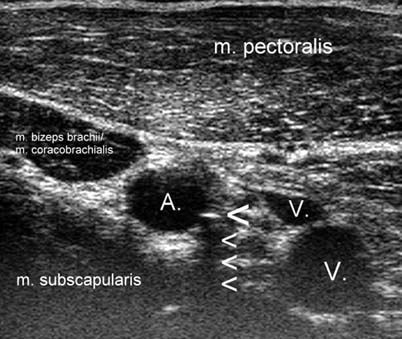

Ultraschallgesteuerte Perivaskulare Axillare